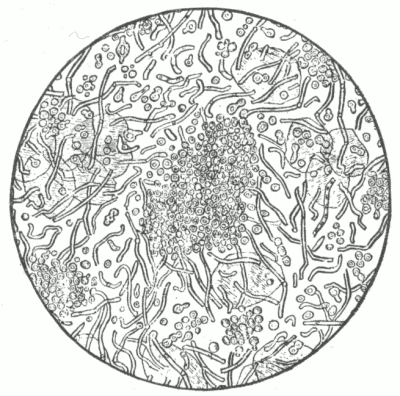

Fig. 8.

Demodex Folliculorum, X 300. Ventral surface. (After Simon).

To what may comedo often be ascribed?

To disorders of digestion, constipation, chlorosis, menstrual disturbance, lack of tone in the muscular fibres of the skin, the infrequent use of soap, and working in a dirty or dusty atmosphere. [Pg 40] A small parasite (demodex folliculorum, acarus folliculorum) is sometimes found in the sebaceous mass, but its presence is without etiological significance, as it is also found in healthy follicles. A microbacillus has been found by several observers, and credited with etiological influence.